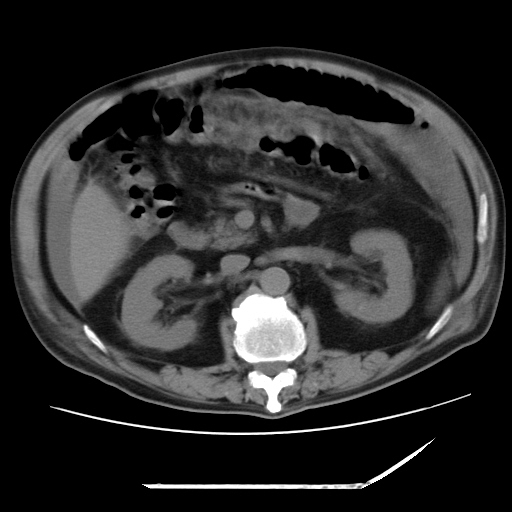

以下是引用zxl51642在2009-8-12 18:55:00的发言:[br]1、肠系膜脂肪浑浊,密度增高,腹水,支持腹膜炎诊断;2、右肾盂及输尿管中段结石,左输尿管起始段结石;3、胆囊切除术后改变?4、双侧胸膜腔少量积液;5、胰腺体积不大,勾勒清楚,肾前筋膜无增厚,不支持胰腺炎,请结合血尿淀粉酶及临床。